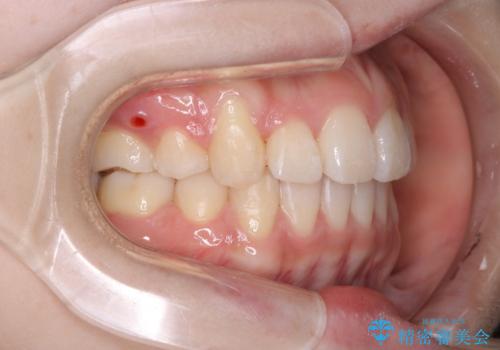

- 4番の歯を4本抜歯をし、上顎にマイクロインプラントを2本埋入し、遠心移動を行いました。

主訴のオープンバイトは改善し、抜歯をしたことで前歯が下がり綺麗になりました。抜歯矯正でしたが1年2か月という短い期間で終了しました。